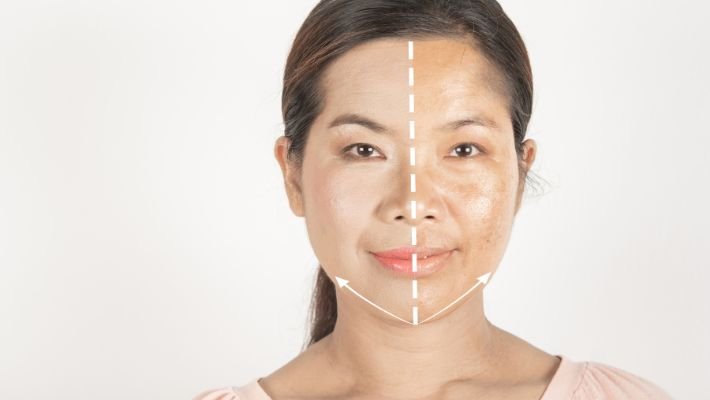

Richen Skin

At Richen Skin, we are dedicated to delivering advanced skin and aesthetic care with precision, professionalism, and a personal touch. We offer a wide range of treatments, including laser therapies, chemical peels, clean-ups, and more, all tailored to meet the unique needs of your skin.

Our team of experienced specialists combines medical expertise with the latest “Gold Standard” technology to ensure safe, effective, and visible results for all skin types. Whether it'...

We offer a number of treatments with precision and artistic vision to reveal each patient's unique beauty.